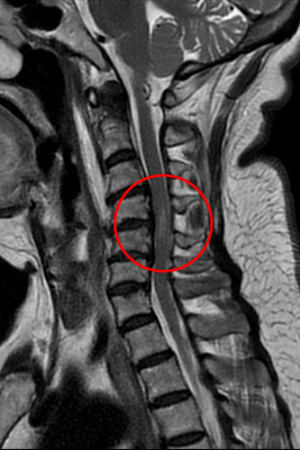

72歲徐姓婦人車禍後被送往花蓮慈濟醫院急診,神經外科部神經血管介入治療科主任李建輝會診時觀察到她僅能用腹式呼吸,加上手腳肌力僅剩二至三分,研判頸椎神經可能受損,進一步以磁振造影檢查確認是頸椎第四到六節之間的神經遭到骨刺壓迫,且已造成脊髓損傷。經李主任緊急以脊椎內固及融合微創手術治療,再經過中醫針灸和積極復健,病人於術後半個月即可下床,靠輔具行走,目前恢復良好。